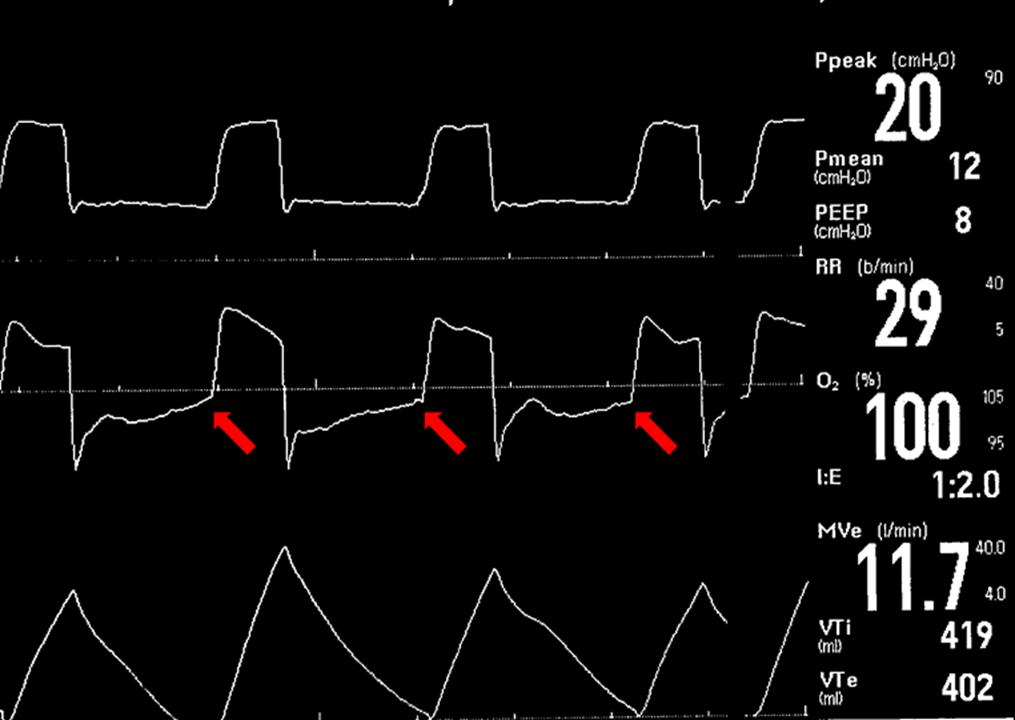

在监测哮喘患者气管插管时,寻找空气潴留是关键。在下面的通气曲线轨迹中,注意中间的流量轨迹不会在下一次呼吸之前返回到基线。(红色箭头)这表示下一次呼吸时患者仍在呼气,导致空气滞留。在呼吸机上看到这种模式可能是空气潴留的早期线索。如果你在照顾这个病人,你会怎么处理这个空气潴留?

在这个病人中,你可以先降低呼吸频率,如果病人呼吸过度,可以增加镇静。I:E比率只有1:2,因此更改I时间使比率为1:3或1:4也是合适的。同时,持续使用支气管扩张剂来减少与本病相关的支气管痉挛,也可以减轻过度的auto-peep。

回想一下,要量化空气滞留所产生的压力,你应该通过检查呼吸机上的呼气控制按钮来检查autoPEEP。在这种追踪中,什么是auto-peep,或内源性peep?总peep是多少?

内源性PEEP是11,总的PEEP是12。这表明患者仅设置为1个PEEP(一个不寻常且不推荐的设置,在这种情况下仅用于演示目的)